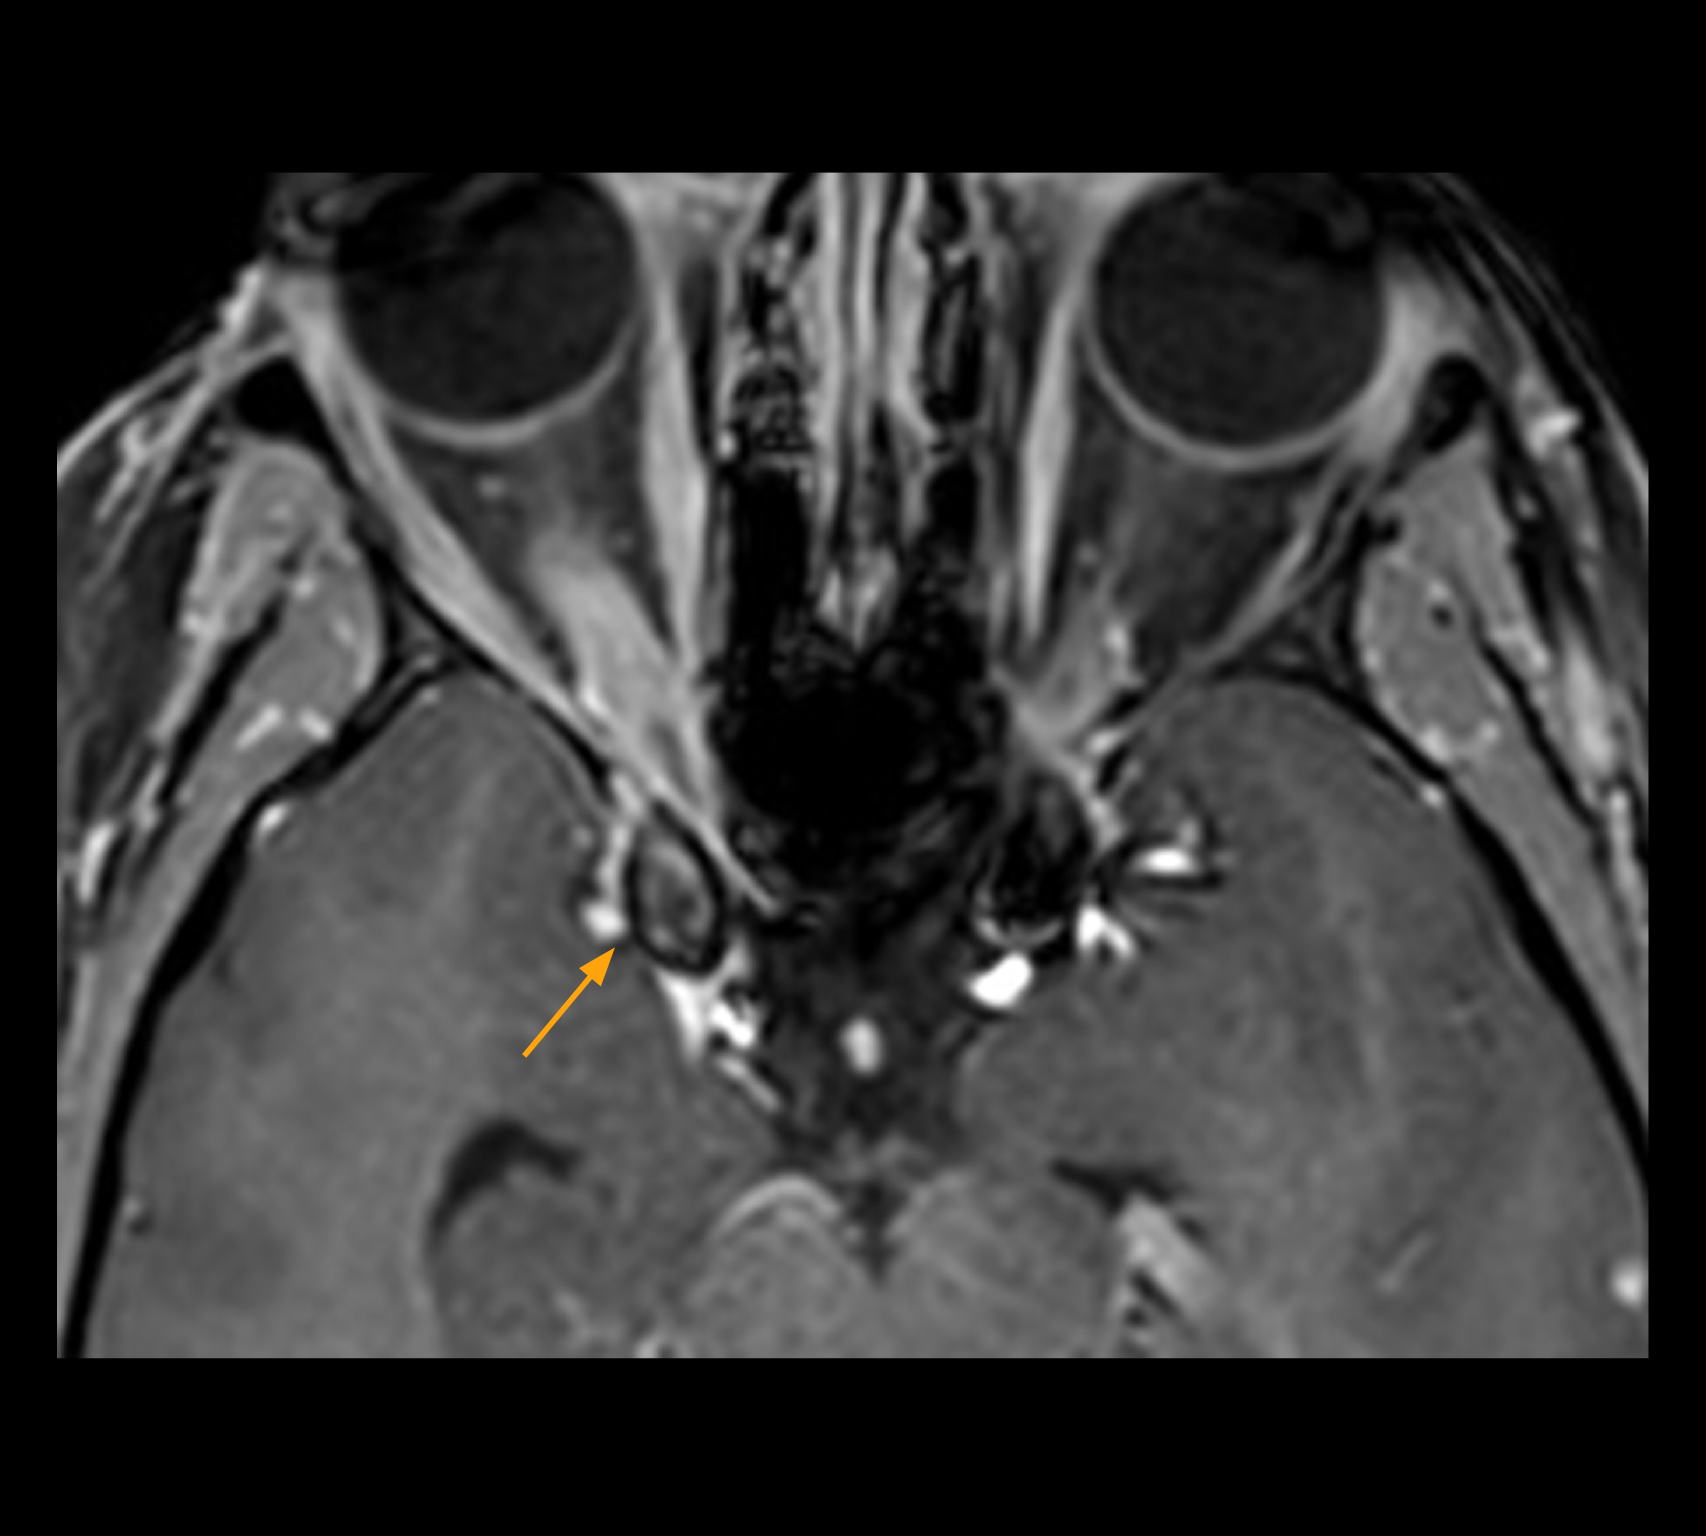

In select cases, the MR 7700 has helped the hospital’s physicians more clearly visualize pathology. “We’re definitely getting the impression that tumors are better delineated with the MR7700,” Dr. Heindel says. “For example, I examined a patient who had been diagnosed in another hospital with possible neuritis of the optic nerve. However, the MR 7700 images allowed me to diagnose it as an optic nerve sheath meningioma, a rare and often misdiagnosed, slowly growing tumor that wascausing the visual disturbances in the patient. The lesion was so well delineated on the high resolution MR 7700 images that our neurosurgeon decided he did not need a biopsy before proceeding directly with decompression of the optic canal and peeling away those tumor cells.”

High-resolution MRI impressively demonstrates the compression and narrowing of the right optic nerve in this case of optic nerve sheath meningioma (ONSM). The coronal T2-weighted images show the hyper-intense, half-moon shaped lesion, that is clearly visible in the axial T1W image after contrast injection (right). These imaging findings were so convincing that there sponsible neurosurgeon did not consider a pretherapeutic histological clarification.

High resolution-MRI impressively demonstrates the compression and narrowing of the right optic nerve in this case of optic nerve sheath meningioma (ONSM). The coronal T2-weighted images show the hyper-intense, half-moon shaped lesion, that is clearly visible in the axial T1W image after contrast injection (right). These imaging findings were so convincing that there sponsible neurosurgeon did not consider a pretherapeutic histological clarification.